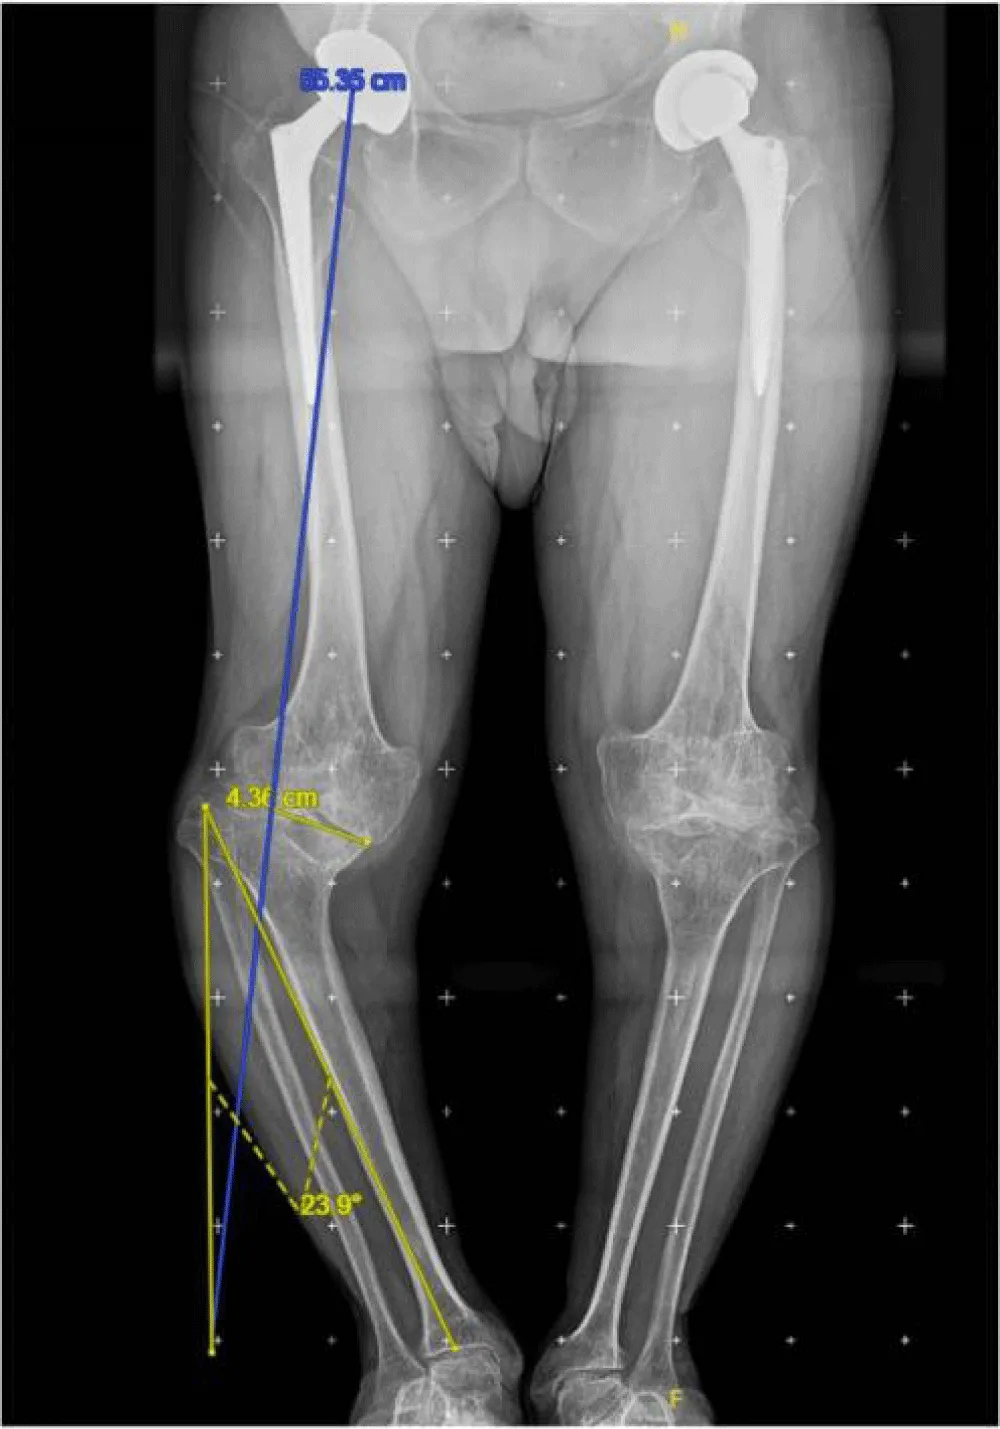

During the physical examination, the patient’s height was measured at 1.22 meters, weight at 46 kilograms, and body mass index was calculated to be 22.1. The right knee showed severe malalignment with a 36.4° extra-articular varus deformity, multidirectional instability, and a range of motion from 0° to 80°. The left knee displayed clinical and radiological signs of moderate osteoarthritis, with minimal discomfort. There were no discrepancies in the length of the lower limbs. In addition, he had previously undergone bilateral total hip arthroplasty, with satisfactory clinical results.

X-rays reveal severe deforming osteoarthritis of the right knee with a medial tibial metaphyseal angle of 53.6° (Figure 1). Telemetry shows medialization of the weight-bearing axis of the right lower extremity due to severe genu varum (Figure 2). Computed tomography (CT) confirms joint destruction with varus deformity of the proximal tibia (Figure 3), and severe misalignment of the posterior tibial slope (Figure 4).